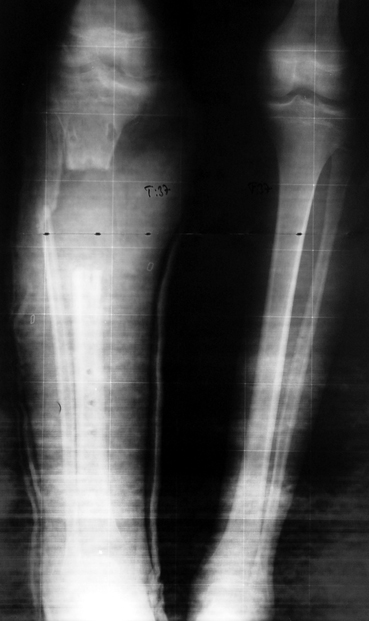

Case 2